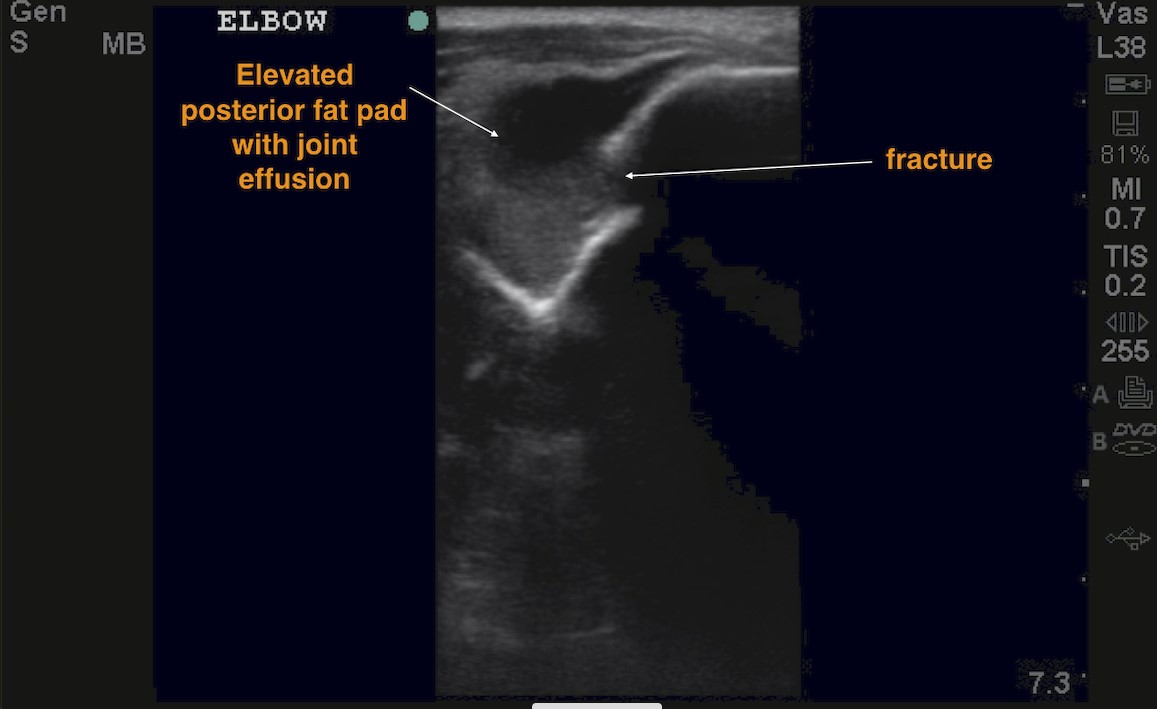

In obvious cases, you will see direct fracture signs (ie, disruption of the cortex). However, for more subtle fractures, use POCUS to look for an elevated dorsal fat pad, caused by a joint effusion that may be an indirect sign of a fracture.5 By identifying a positive dorsal fat pad sign and/or cortical lesions of the distal humerus, Supracondylar fractures can be detected very sensitively by POCUS. One study found that for ultrasound, fracture diagnosis in comparison to radiographs had a sensitivity of 100%, a specificity of 93.5%, an NPV of 100% and PPV of 95.2%.6

Bulging posterior fat pad: rise of the fat pad (Sail sign) above the extension of the distal humeral line on longitudinal view (Figure 4) or above a line connecting both lips of the olecranon fossa on transverse view (Figure 5).

Figure 5: Transverse axis of the elbow depicting the olecranon fossa and a large joint effusion with a disruption of the cortex.